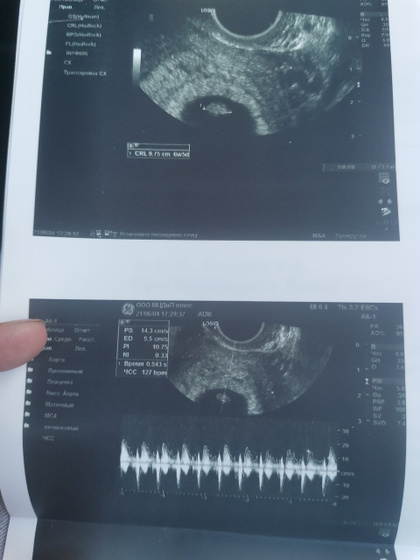

Всем приветик?была сегодня на узи) растем потихоньку ктр 7мм?сладкая моя крахотулечка?и наконец то я услышала сердцебиение❤️124 удара в минуту❤️это незабываемые впечатления???